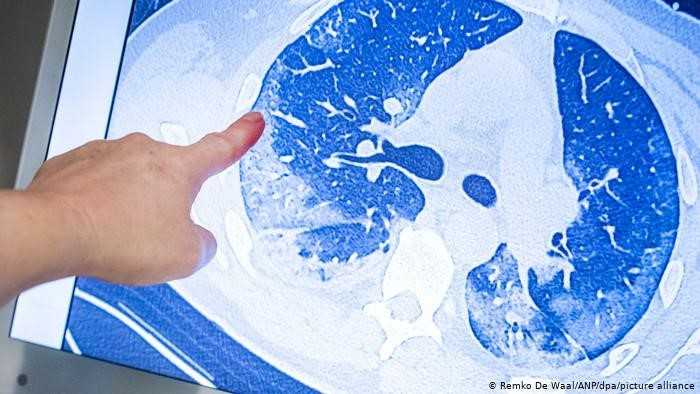

Hầu hết người bệnh COVID-19 sẽ không thể hồi phục sức khỏe hoàn toàn và có nguy cơ gặp phải các di chứng như đau nhức cơ, mệt mỏi, trầm cảm. Kể cả những bệnh nhân đã khỏi bệnh được 6 tháng cũng mắc phải các triệu chứng trên, theo công bố của các nhà khoa học trên Tạp chí chuyên ngành Lancet.

Hầu hết người bệnh COVID-19 sẽ không thể hồi phục sức khỏe hoàn toàn.